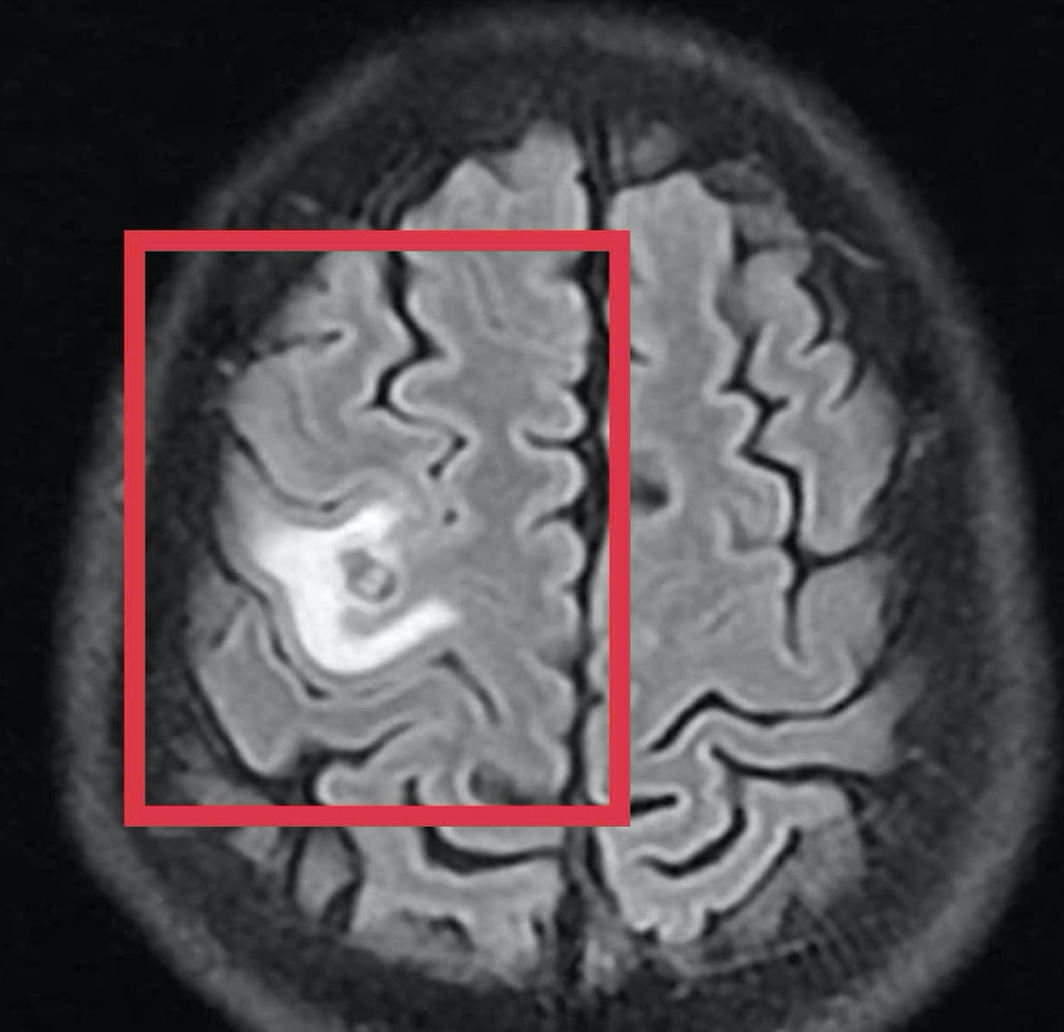

Kết quả chụp cộng hưởng từ (MRI) sọ não cho thấy một tổn thương dạng nang nhỏ tại thùy trán trái, kích thước khoảng 11 x 7 mm, xung quanh có phù não nhẹ. Hình ảnh này không điển hình cho u não nguyên phát mà hướng nhiều hơn đến tổn thương do ký sinh trùng.

Để làm rõ nguyên nhân, các bác sĩ đã chỉ định thêm các xét nghiệm huyết thanh học. Kết quả cho thấy bệnh nhân dương tính với kháng thể kháng sán dây chó – yếu tố quan trọng giúp khẳng định chẩn đoán tổn thương não do ký sinh trùng.

Khi tái khám gần một tháng sau, kết quả chụp MRI cho thấy tổn thương não thu nhỏ rõ rệt, phù não giảm, không còn dấu hiệu tiến triển. Bệnh nhân được chỉ định thêm một đợt thuốc củng cố và theo dõi lâu dài.